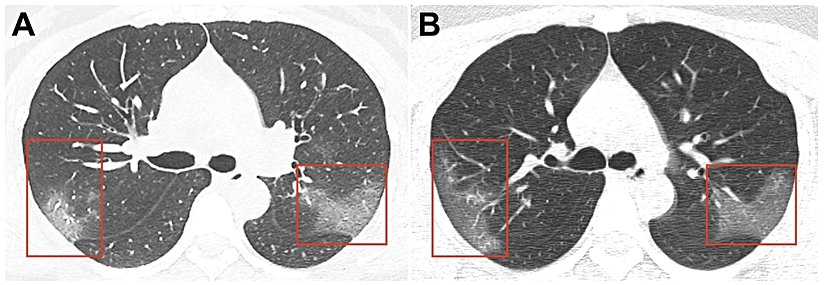

Mevcut koronavirüs hastalarının akciğer taramalarında, sıvının akciğerlerde biriktiği ve beyaz lekeler olarak göründüğü bir durum olan "buzlu cam (ING: ground glass)" görünüyor.

Aşağıdaki taramalar, farklı zamanlarda aynı hastadan alınmış. Kişinin akciğerindeki "buzlu cam"ın hastalık ilerledikçe daha da belirginleştiği görülüyor.

İlk bulgular, nefes darlığına geçen sürenin 5 gün, hastaneye başvurmaya kadar geçen sürenin 7 gün, Akciğer Solunum Yetmezliği bulgularına kadar geçen süre 8 gün, YBÜ yatışa kadar geçen süre 10 gün olduğunu gösterdi. Hastaların çoğunun hastaneye yatış sırasında çekilen Akciğer Bilgisayarlı Tomografilerinde; çift taraflı buzlu cam alanları ve yama şeklinde tutulum vardı.